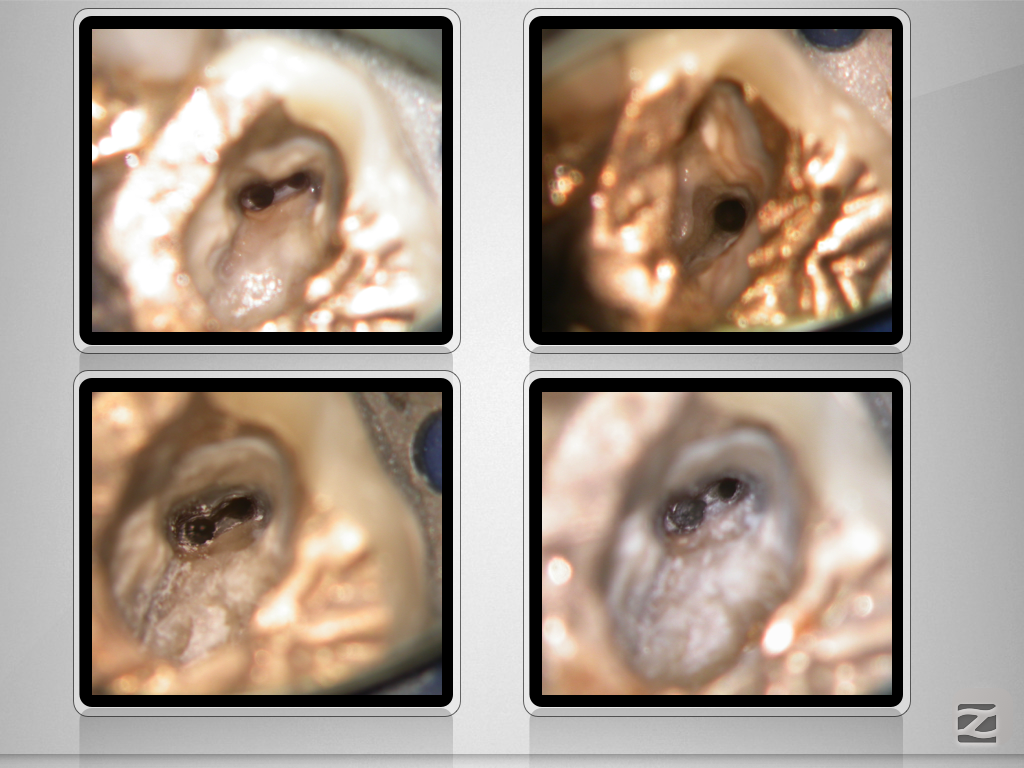

16D.014

Immer schön skeptisch bleiben 4